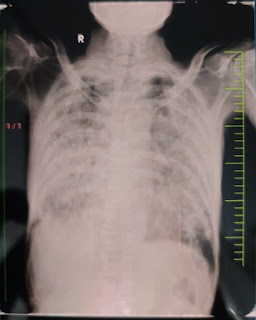

On admission - chest xray showing bilateral infiltrates with consolidation